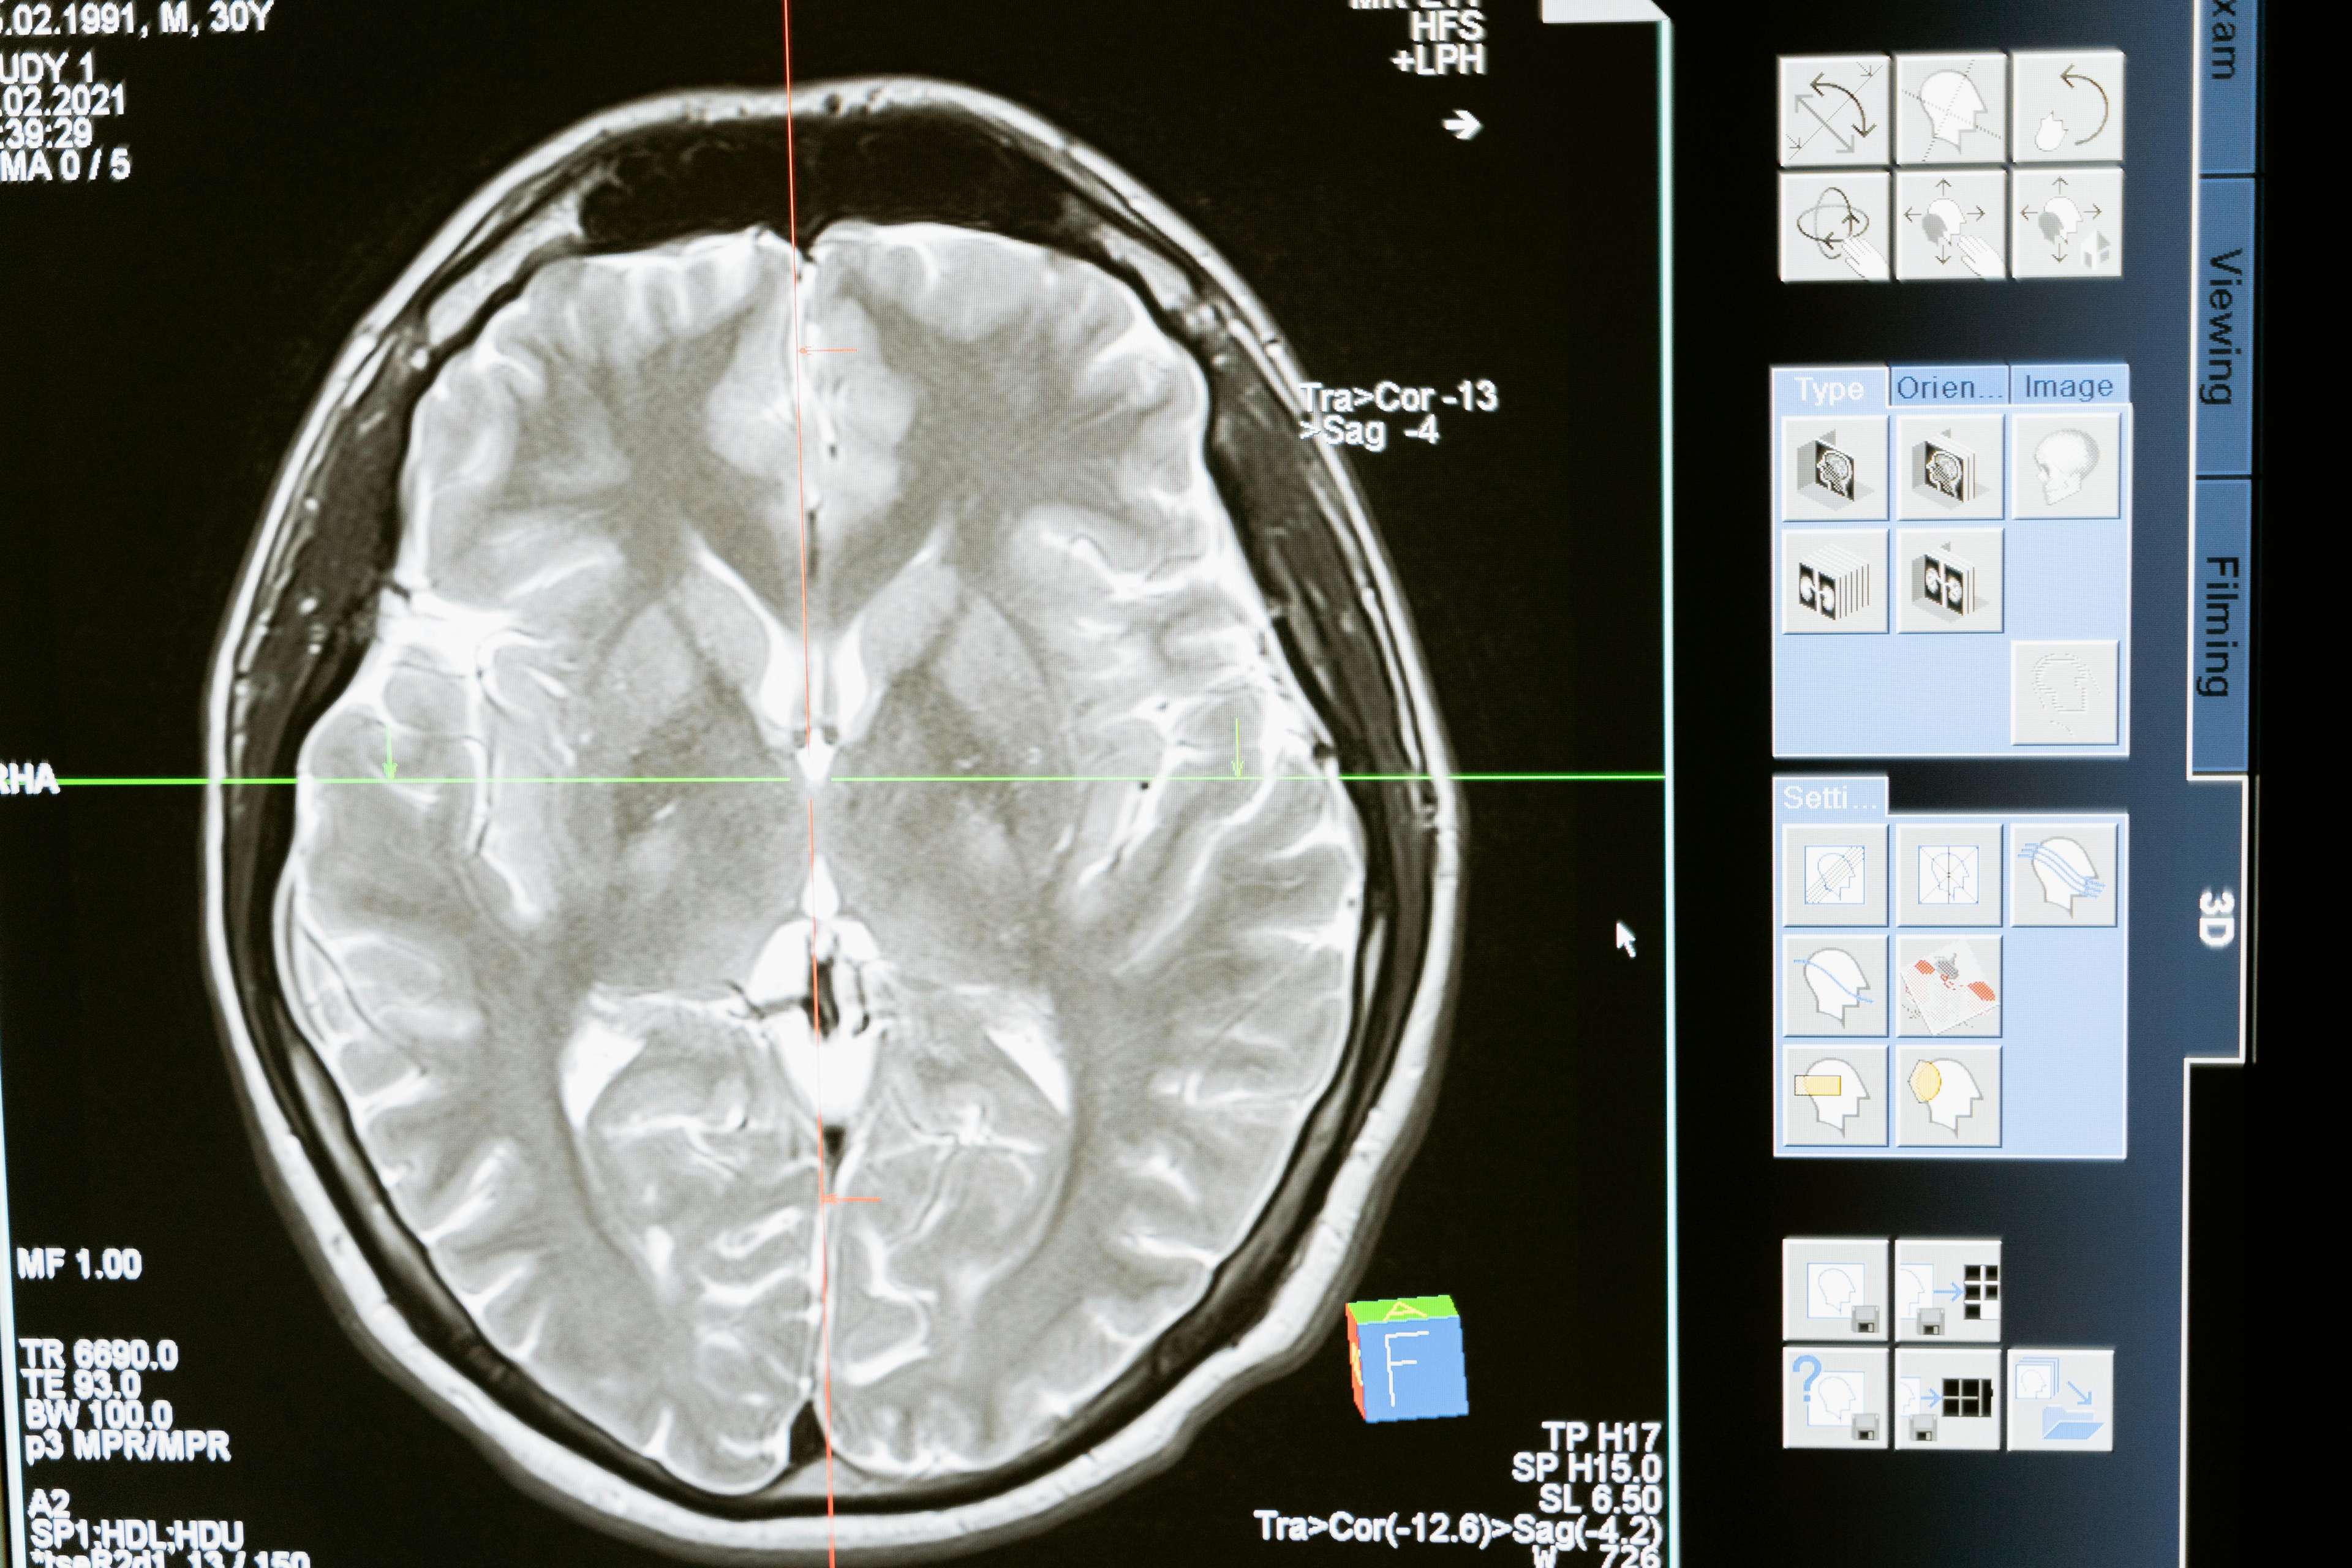

В 1990-х годах прорыв в медицинских технологиях дал новую надежду пациентам с болезнью Паркинсона. Было доказано, что глубокая стимуляция мозга, хирургическая процедура, включающая в себя имплантацию устройства, доставляющего электрические импульсы в определенные области мозга, значительно улучшает двигательные функции и уменьшает симптомы. Воздействуя на области мозга, отвечающие за двигательный контроль, DBS помогает регулировать аномальную мозговую активность, позволяя пациентам восстановить контроль над своими движениями.